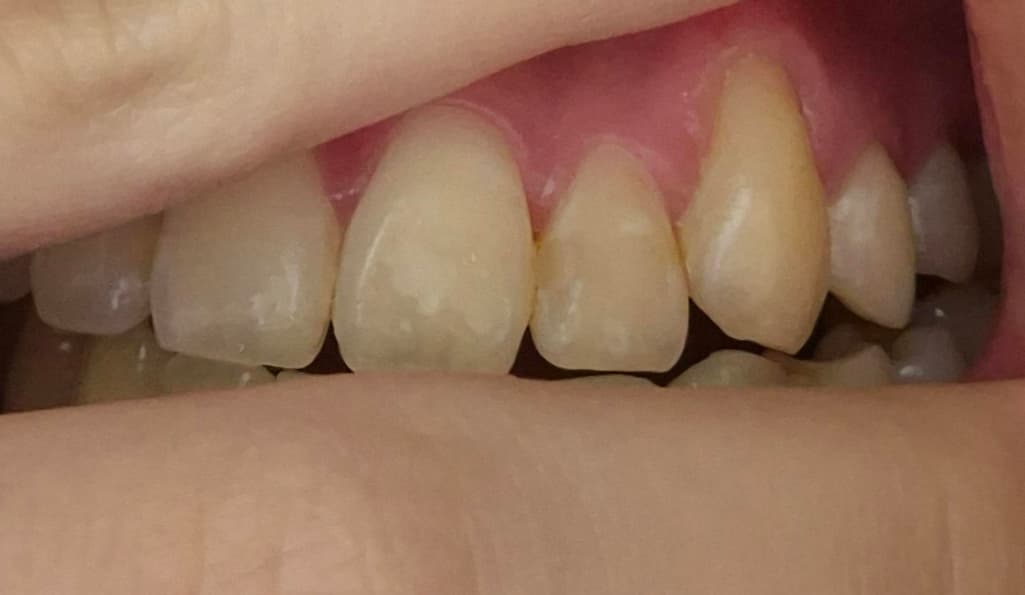

24살 여자 잇몸 퇴축이 심한 걸까요?

교정했고 24살 여자입니다..

잇몸퇴축이 너무 심한 거 같은데 치료가 필요할까요?

사진으로 봤을 경우에는 잇몸 퇴축이 조금 진행된 것으로 보입니다. 잇몸 대축은 잇몸에 너무 강한 자극이 가해지면서 생기기 때문에 양치질을 할 때 잇몸에 넘어가는 자극이 가해지지 않다고 하는 것이 좋습니다.

나이 대비하여 잇몸이 조금 퇴축된 것은 맞습니다. 지금부터 관리를 더 잘해주셔야겠습니다.

사진상으로 보면 잇몸에는 문제가 없어 보입니다 지금처럼 관리 하시면 괜찮을것같습니다.

송곳니는 원래 잇몸퇴축이 다른 치아보다 먼저, 더 많이 이뤄집니다 교정 후 잇몸퇴축이 동반되는 것은 흔한 부작용 중 하나이고요 앞으로 잇몸관리 꾸준히 치과에서 받으세요